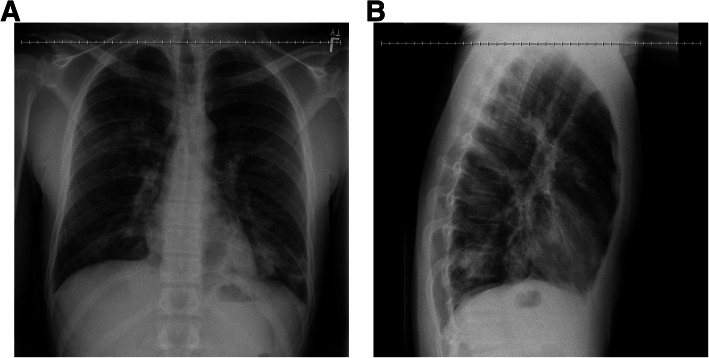

On admission, he was tachypneic and tachycardic with leukocytosis and lymphopenia. An initial chest x-ray revealed patchy infiltrates of the right upper and bilateral lower lobes that were consistent with multifocal pneumonia (Fig. 1). A respiratory pathogen panel was positive for Influenza A (real time polymerase chain reaction test on nasal swab), and, in a few days later, his sputum grew methicillin-sensitive Staphylococcus aureus (MSSA). Tests for other pathogens were negative. Upon admission to the intensive care unit (ICU), his initial complete blood count (CBC) was remarkable for white blood cell count (WBC) of 9.8 k/gL with 92.4% neutrophils and 3.8% lymphocytes and a platelet count of 97 k/ gL. His basic metabolic panel (BMP) was remarkable for creatinine of 2.34 mg/dL, AST of 343u/L, ALT of 144u/L, lactic acid of 9.8 mMol/L, and procalcitonin of 26.86 ng/mL. Ferritin was elevated at 5181 ng/mL during the hospitalization.

He had no clinical history of inhalational injury other than the vaping exposure. He had severe progressive refractory respiratory failure despite maximal ventilatory strategies with a progressive increase in airway pressure and dropping Pa02/Fi02 ratio. At this time, he became hypotensive and was vasopressor dependent. Treatment was started with vitamin C, thiamine, hydrocortisone and multiple antibiotics (vancomycin, cefepime, azithromycin and doxycycline) for concern of sepsis as well as oseltamivir for Influenza A. Despite antibiotic treatment, his hypoxic respiratory failure further progressed and he required aggressive ventilatory support with a positive end-expiratory pressure (PEEP) of up to 30. The patient’s Pa02/Fi02 ratio was only 37 when the extracorporeal membrane oxygenation (ECMO) team was contacted and a bilateral femoral veno-venous (V-V) ECMO was placed at the spoke institution as part of our mobile ECMO program and patient was brought to our hub institution. After the procedure he was stable enough to be transferred to our facility. Despite the V-V ECMO, the patient required multiple vasopressors and although his lactic acid decreased initially, there was a progressive need for escalatory support and patient was converted patient from V-V ECMO to veno-arterial (V-A) ECMO. Given severe sepsis with shock, the peripheral V-A ECMO was deemed to be insufficient to provide hemodynamic support, and he was subsequently placed on central V-A ECMO to improve end-organ function. The patient’s clinical course was complicated by acute kidney failure for which he required dialysis, liver failure and encephalopathy which was likely secondary to his metabolic derailment and sepsis. He also experienced multiple episodes of atrial fibrillation with rapid ventricular response for which he was successfully cardioverted three times. A transthoracic echocardiogram showed a severely dilated right ventricle as well as biventricular systolic dysfunction. Due to a worsening pulmonary edema, he was emergently placed on an intra-aortic balloon pump (IABP). Although the CXR showed subsequent improvement in aeration with improvement in minute ventilation on the ventilator (Fig. 3), the patient also developed severe limb ischemia with skin mottling and ecchymoses on his extremities, trunk, nose and ears. Sepsis and cytokine storm with severe vasoplegia requiring vasopressors were determined to the ongoing issue. Severely diminished tibial flow and thrombi in the bilateral posterior tibial arteries was seen on vascular ultrasound and out of concern for compartment syndrome the patient underwent a fasciotomy. During this time, patient was awake, alert and communicative with the family at the bedside. Despite our best efforts, non-viable muscle was seen in all four compartments bilaterally and a bilateral through-knee amputation was performed. Confronted with the patient’s poor prognosis, the family decided to suspend life-supporting measures in favor of transition to comfort care. The patient expired shortly after the IABP and ECMO were turned off. In total, the patient spent two weeks in the hospital. The family consented to an autopsy.